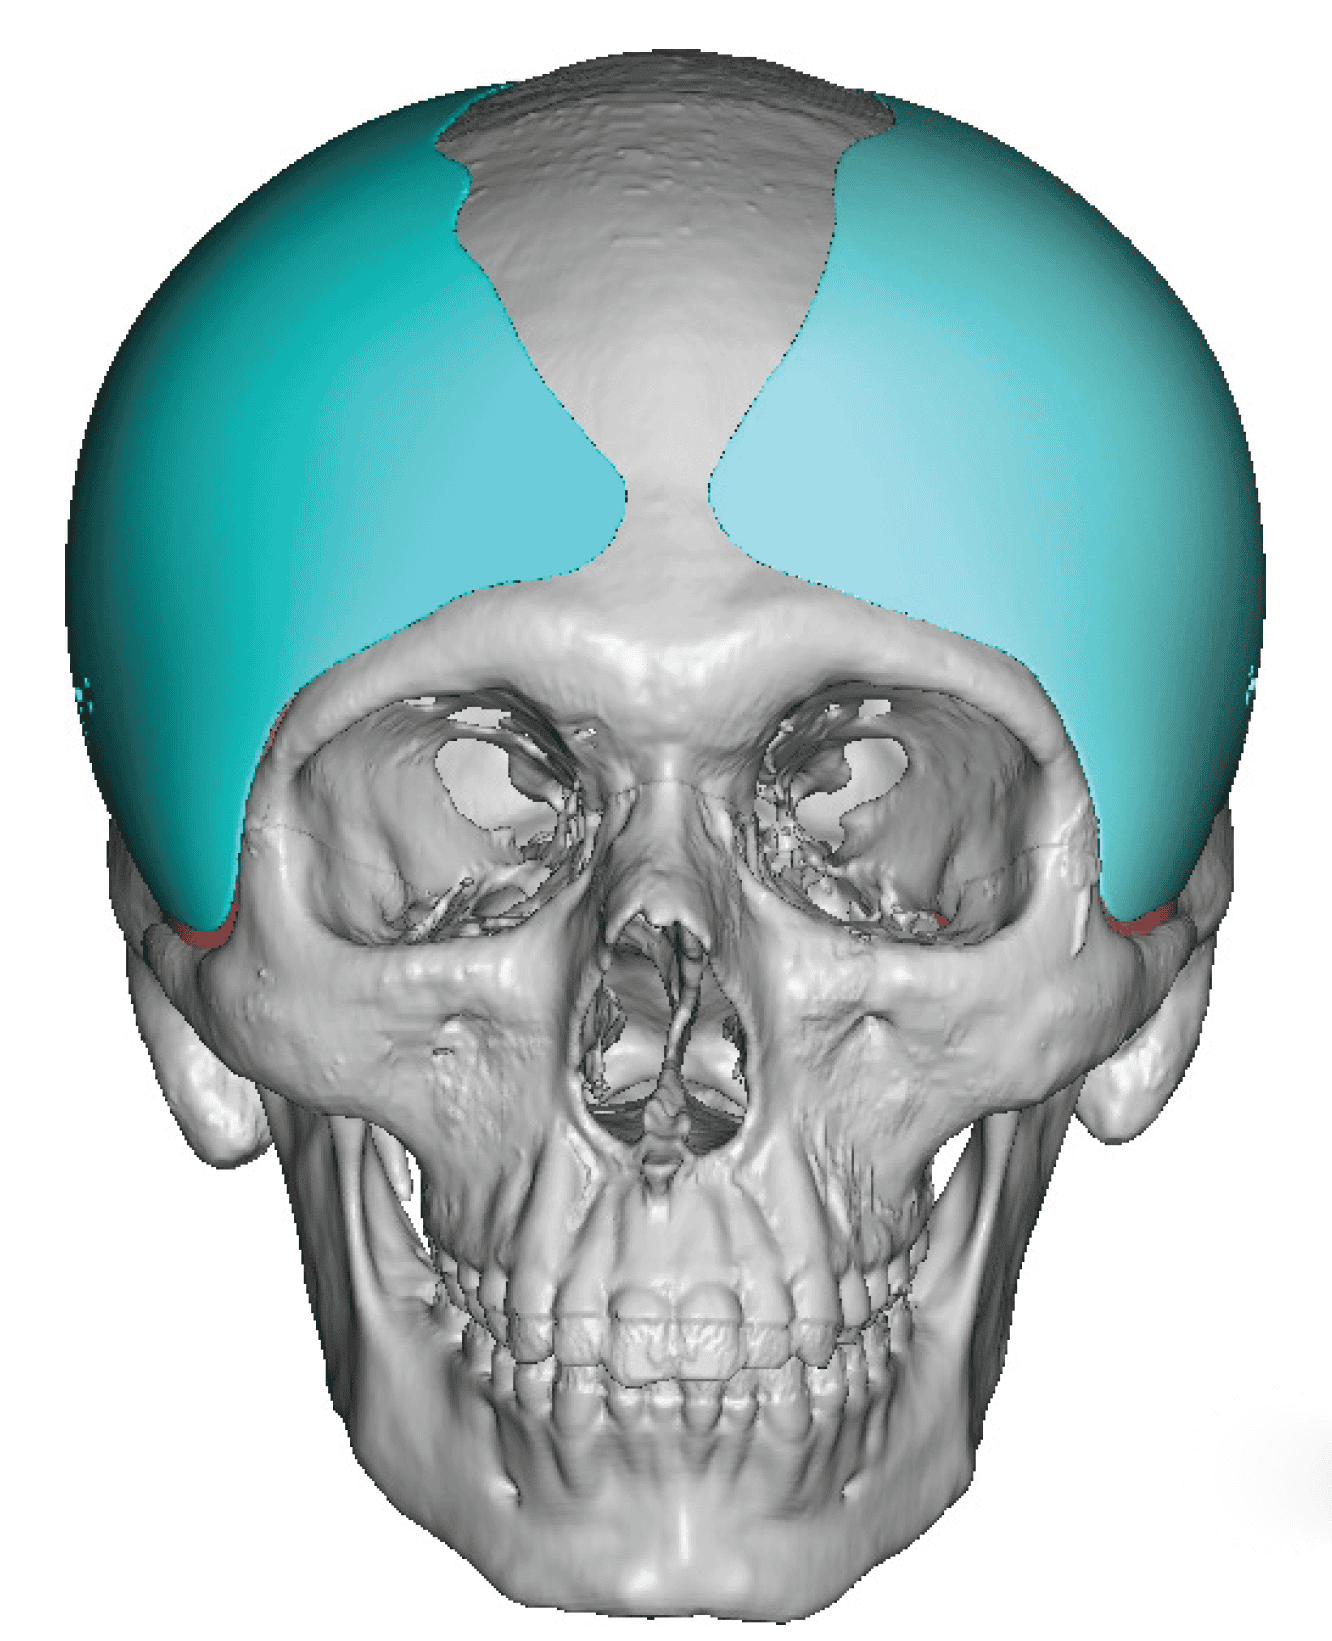

Patient 27

Desire for reduction of skull ridge reduction.

Anterior sagittal skull ridge reduction by bone burring.

Desire for reduction of skull ridge reduction.

Anterior sagittal skull ridge reduction by bone burring.